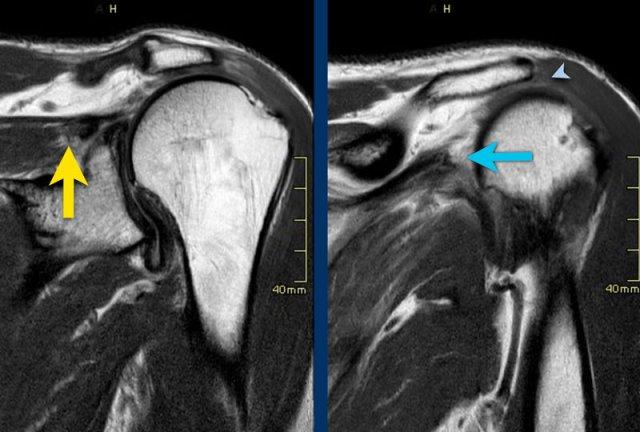

Ca lâm sàng 1

Các hình ảnh cho thấy khoang dưới mỏm cùng vai bị hẹp (đầu mũi tên) thứ phát sau rách chóp xoay với sự co rút của cả gân trên gai (mũi tên vàng) và gân dưới gai (mũi tên xanh).

Ca lâm sàng 2

Bệnh nhân này có khoang dưới mỏm cùng vai bị hẹp.

Lưu ý rằng tình trạng hẹp được thấy rõ trên hình chụp vai ở tư thế xoay ngoài, trong khi không quan sát được trên hình chụp ở tư thế xoay trong.